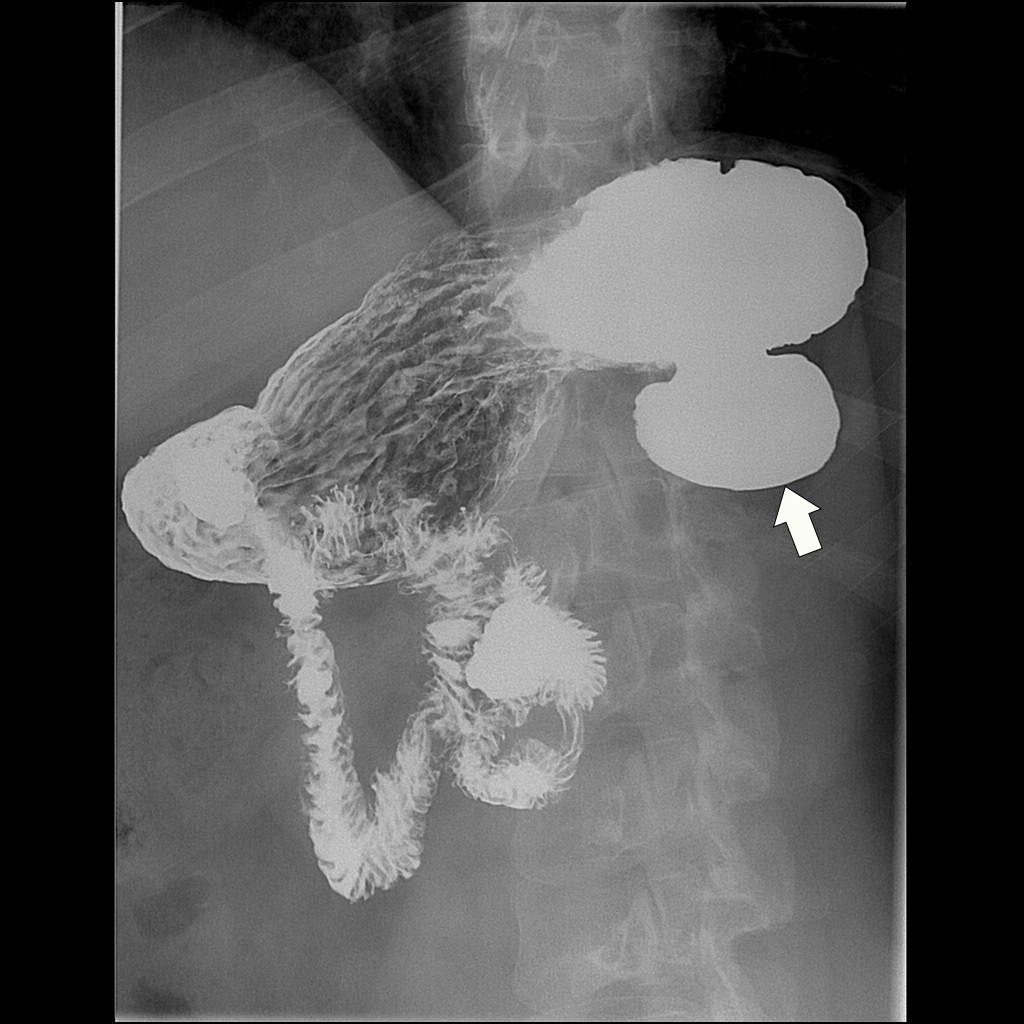

Below: A radiograph showing a large gastric diverticulum (arrow) on a barium study.

Source: Bickle, I. (2020). Gastric diverticulum. Radiopaedia. https://radiopaedia.org/cases/gastric-diverticulum-12